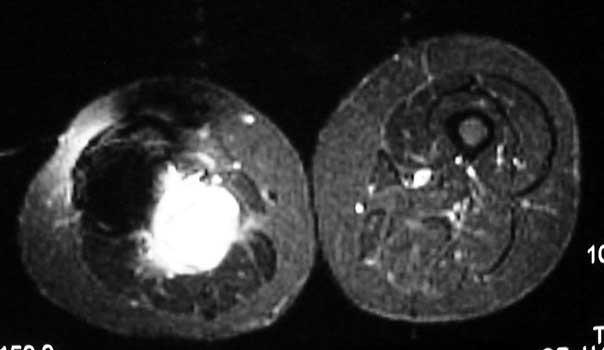

Recurrent osteosarcoma in patient status post resection of femur and placement of modular endoprosthesis. Axial T1 and STIR sequences clearly demonstrate mass adjacent to endoprosthesis.